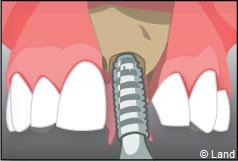

Un implant dentaire est une racine artificielle, placée par le chirurgien-dentiste dans l’os alvéolaire de l’un des maxillaires en remplacement de la racine d’une dent extraite, qui servira de support à une prothèse. Sa forme est généralement cylindrique ou légèrement conique, ressemblant à une vis, en titane ou en zircone, avec une connexion au niveau supérieur, à l’emplacement de la gencive, pour permettre la pose d’un élément prothétique par vissage ou scellement. Son diamètre varie entre 3 et 5 mm et sa longueur entre 8 et 15 mm. La pose d’un implant, réalisée sous anesthésie locale, est totalement indolore. Elle se pratique au cabinet dentaire ou en clinique.

Le chirurgien-dentiste après une anesthésie locale pratique une incision, puis il décolle la gencive pour accéder à l’os alvéolaire.

Ensuite il prépare l’emplacement de l’implant dans l’os en passant plusieurs forets de diamètre croissant. Le forage de l’os se fait à vitesse maîtrisée et lente sous irrigation, pour respecter la structure osseuse et éviter tout échauffement de celle-ci. Le praticien arrête lorsqu’il a obtenu un puits d’un diamètre très légèrement inférieur à l’implant à poser.

L’implant est placé dans l’os le plus souvent par vissage et doit avoir une liaison forte avec l’os. Le praticien replace alors la gencive et pose des points de suture.

Exemple d’un implant unitaire pour remplacer une dent antérieure manquante.